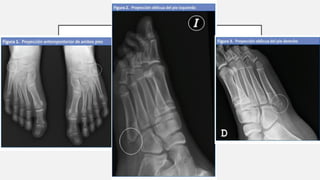

ENFERMEDAD DE ISELIN

Osteocondritis de la

base del 5°

metatarsiano

Tracción excesiva del

tendón del músculo

peroneo lateral corto

Se asocia a inversión

del antepié en atletas

Dolor y edema.

Rx núcleo accesorio

de osificación

(confundirse con

fractura)

Tto. hielo local y

antiinflamatorios. Uso

de órtesis pronadora

del mediopié

ENFERMEDAD DE ISELIN Osteocondritisde la base del 5° metatarsiano Tracción excesiva del tendón del músculo peroneo lateral corto Se asocia a inversión del antepié en atletas Dolor y edema. Rx núcleo accesorio de osificación (confundirse con fractura) Tto. hielo local y antiinflamatorios. Uso de órtesis pronadora del mediopié